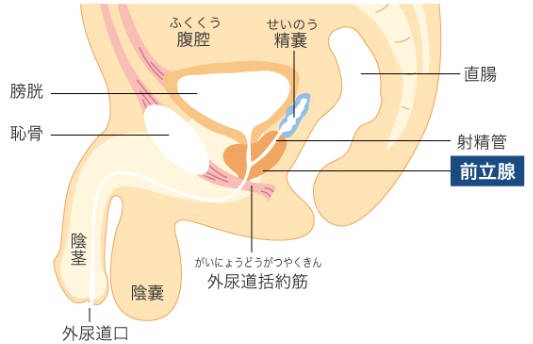

前立腺炎の場合、一般的には会陰部(肛門の前)の鈍痛、 睾丸の鈍痛、排尿痛があげられます。 そして、前立腺炎では多くの場合、この会陰部に痛みが生じます。 会陰部の痛み 急性前立腺炎の場合 急性前立腺炎の場合は、高熱と会陰部痛をともなうため、 男性 会陰部にしこり person 30代/男性 前も相談させて頂きました。 だんなが睾丸のすぐ下から肛門の間にしこりを発見しました。 去年には肛門周囲膿瘍で入院したこともあり、診察を受けに行きましたが、経過は大丈夫で、しこりについては1919 男性 男性の尿道は長く、外尿道口から入った細菌は、膀胱に達する前に排尿によって流されることが多い。前立腺からの分泌液には、細菌の侵入を防ぐ働きがある。 女性 女性は、男性に比べて、尿道が短い上、肛門や膣前庭部と外尿道口が近いので、その分、細菌が膀胱の中に入りやすい。

生殖器の構造 看護roo カンゴルー

男性の生殖器系の構造 21 男性の健康上の問題 Msdマニュアル家庭版

生殖器系 からだのしくみを調べる 医療総合qlife